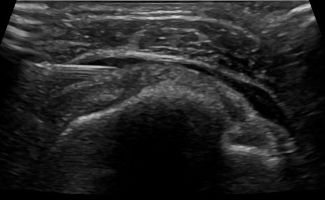

Η καθοδήγηση του υπερήχου εγγυάται τη σωστή και ασφαλή τοποθέτηση του κορτικοστεροειδούς εντός του θυλάκου, αποφεύγοντας την πιθανή έγχυση στον τένοντα, η οποία μπορεί να προκαλέσει φθορά του.

Σε συνδυασμό με την αντιφλεγμονώδη δράση του κορτικοστεροειδούς, η υπερηχογραφική καθοδήγηση παρέχει τη δυνατότητα υδροδιάτασης του θυλάκου πριν την έγχυση του κορτικοστεροειδούς. Η υδροδιάταση περιλαμβάνει έγχυση φυσιολογικού ορού και τοπικού αναισθητικού προκειμένου να εξουδετερωθούν οι συμφύσεις εντός του θυλάκου.